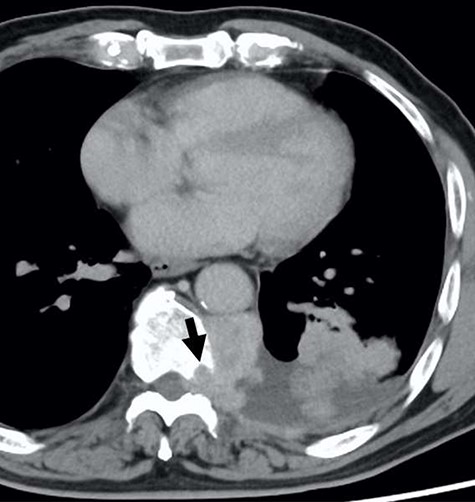

A 78-year-old man complained of chest pain for 2 months and was admitted to our hospital. Computed tomography (CT) scans revealed a tumor in the left thorax. He had undergone prior surgical resection of the primary SFT and recurrent tumor at 11 and 2 years before the current presentation. The CT findings of the primary tumor revealed a solitary, well-circumscribed and no signs of invasion (Fig. 1). Intraoperatively, the primary tumor arose from the visceral pleura and the resection was performed by wedge resection. The resected tumor was an oval, elastic soft mass with homogenous milky white cut surfaces. Postoperative histopathologic and immunohistochemical findings were consistent with SFT, and the mitosis and malignant features, including nuclear atypia, necrosis or higher cellularity, were hardly seen. In contrast to the primary tumor, as shown in Fig. 2, the CT findings revealed that the current tumor extended through the neural foramen. Furthermore, the tumor had an osteoclastic progression into the thoracic spine. Therefore, this tumor was considered to become malignant, and we considered the surgical complete resection is impossible. For histological confirmation, CT guided needle biopsy was performed. The histological findings of this recurrent tumor were identical to those of the primary tumor. The mitosis was hardly seen in this recurrent tumor. However, immunohistochemically, the MIB-1 proliferation index (Ki-67) of the primary tumor and the current tumor was 1.74 and 30.00%, respectively (Fig. 3A and B).

The computed tomographic findings of the primary tumor (arrow).